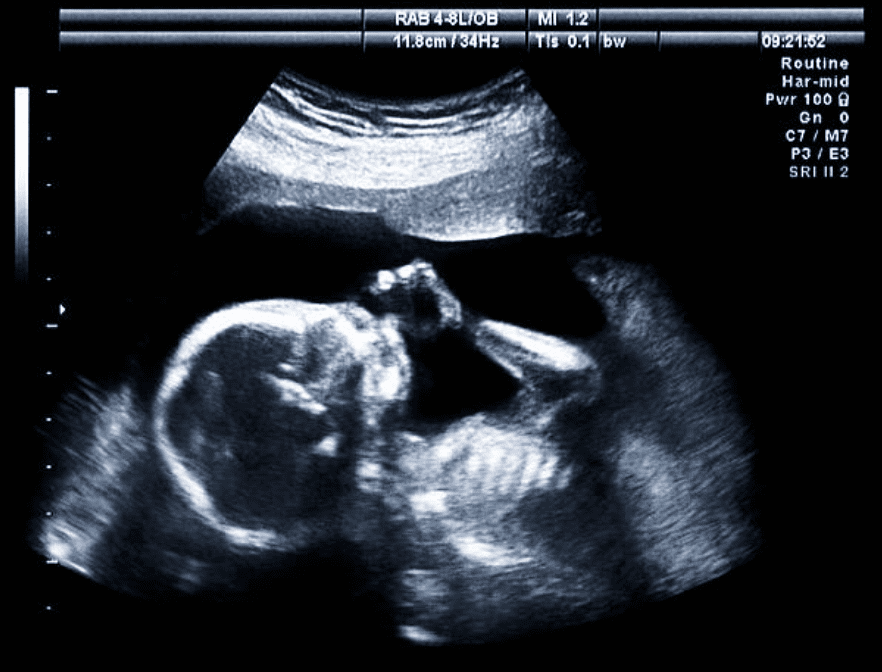

L'imagerie 2D fournit des images en temps réel, claires et sûres du développement du fœtus, assurant une surveillance efficace tout au long de la grossesse.

L'imagerie 2D est largement utilisée dans les soins prénatals en raison de sa fiabilité et de sa sécurité éprouvées. Elle permet aux prestataires de soins de santé de surveiller la croissance du fœtus, d'évaluer les niveaux de liquide amniotique et de détecter toute anomalie en temps réel. Cette méthode d'imagerie est précieuse pour observer le rythme cardiaque, la position et l'état de santé général du fœtus. De plus, l'échographie 2D est rentable et largement disponible, ce qui en fait le choix privilégié pour la surveillance de routine de la grossesse.